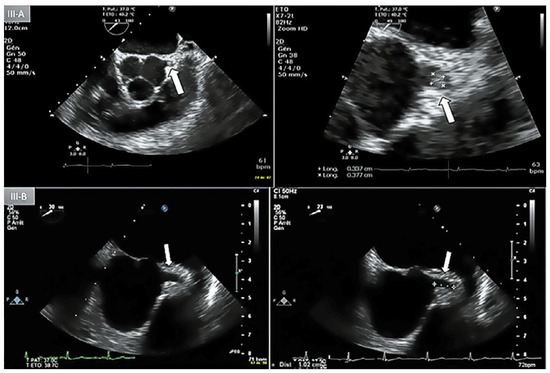

Direct His bundle pacing has recently attracted interest as a more physiological alternative to right ventricular or biventricular stimulation. The advent of new tools has facilitated the implantation procedure. This report relates our initial experi...